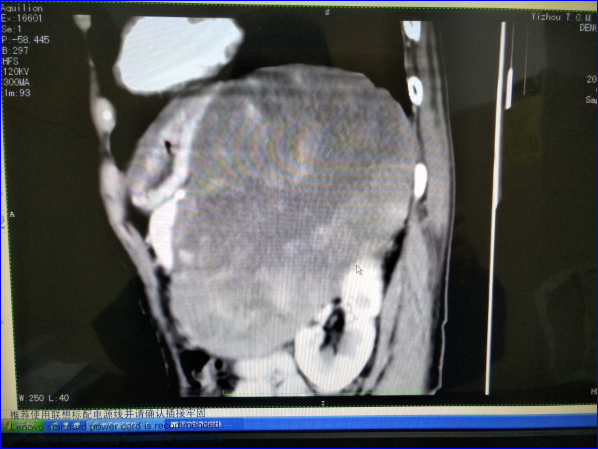

矢状面CT片显示,该肿瘤已压迫到患者肾脏、脾脏、胃和胰腺等器官,胰腺被顶起,肾脏受压几近一半,顶住膈肌上抬,腹腔、胃部被挤压空间狭窄。